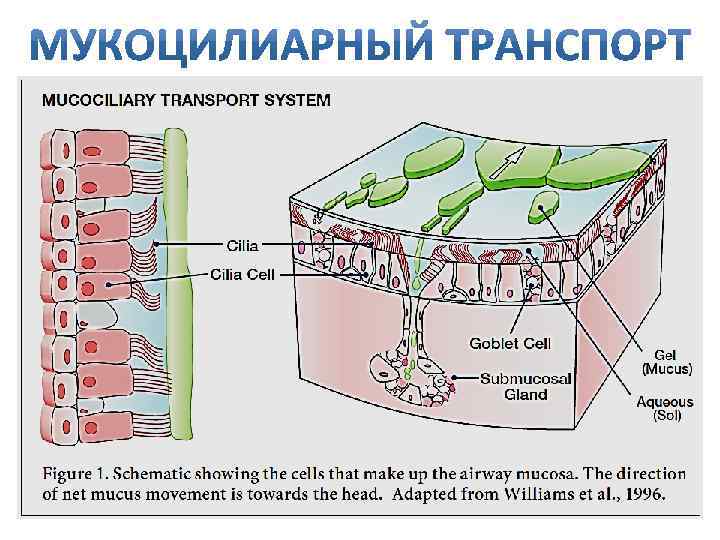

Механизм защиты легкого Слизь (зеленый цвет) нейтрализует и связывает патогенную флору(синий цвет) Слизь – это барьер между клетками и патогенной флорой Слизь – это транспортное средство

Механизм защиты легкого Слизь (зеленый цвет) нейтрализует и связывает патогенную флору(синий цвет) Слизь – это барьер между клетками и патогенной флорой Слизь – это транспортное средство